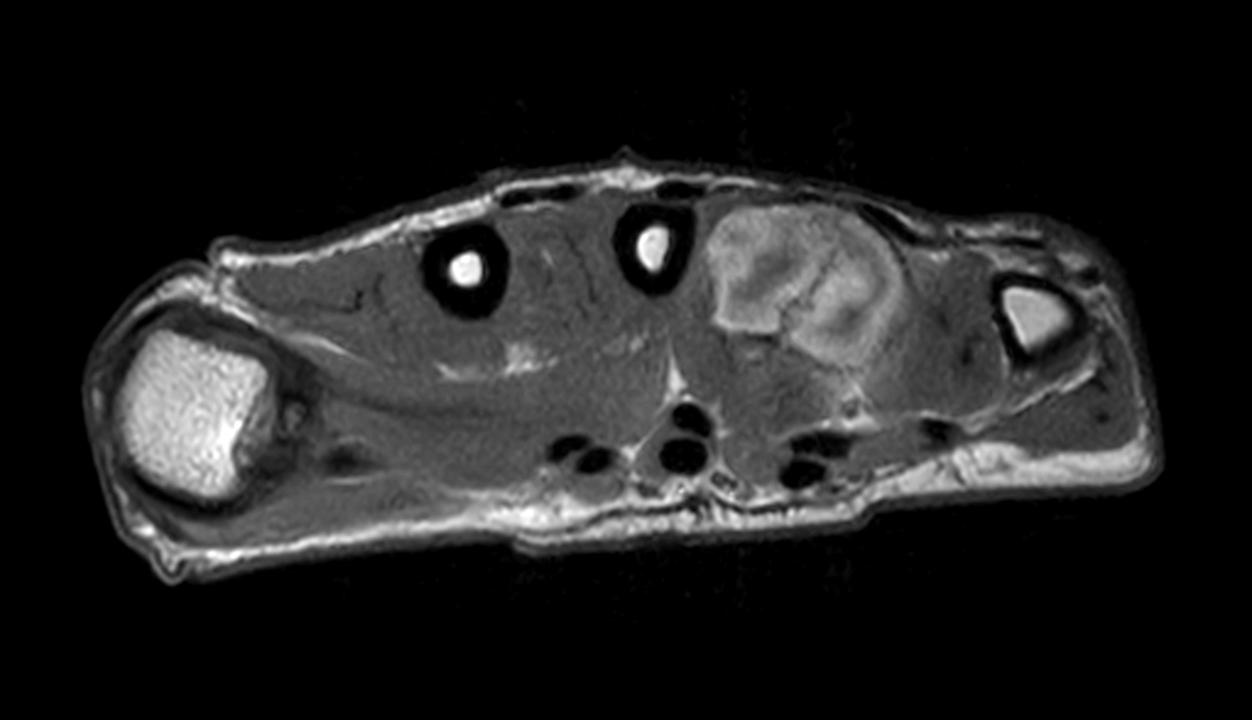

Axial T1w mDIXON XD TSE (Water only) (with gado)

Axial T1w mDIXON XD TSE (In Phase) (with gado)

Axial T1w mDIXON XD TSE (Partial FatSat) (with gado)